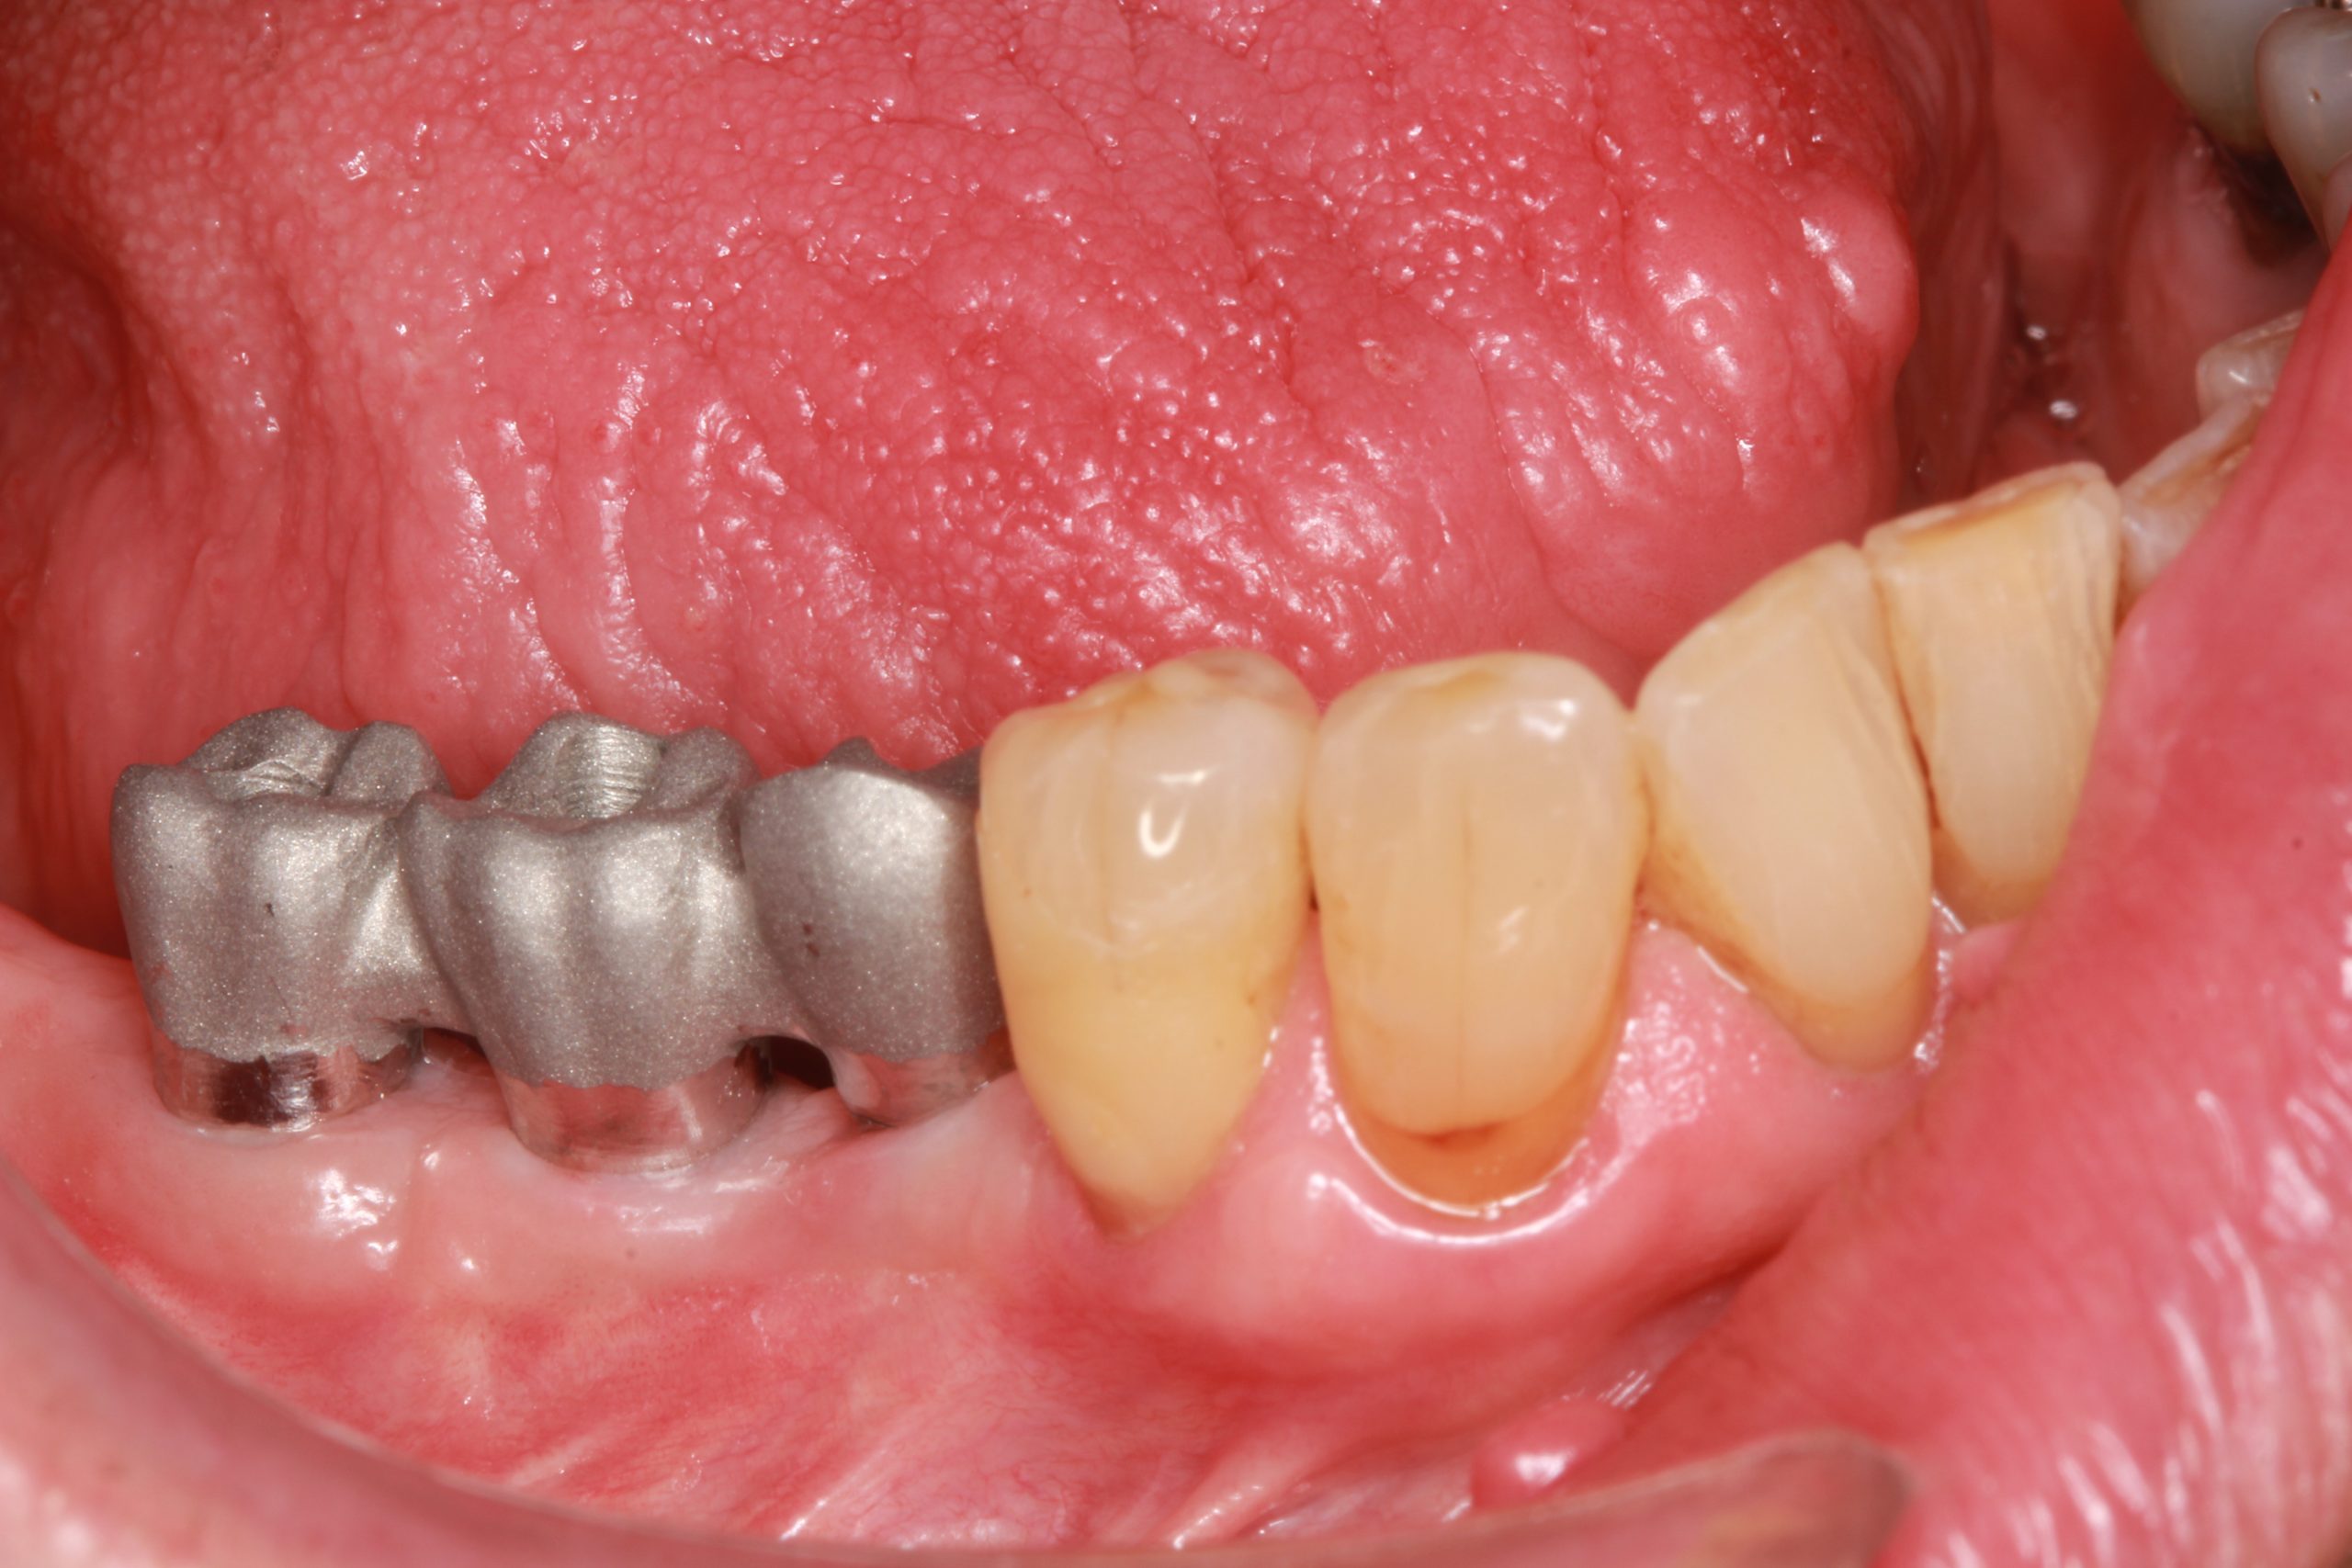

A fixed screw-retained metal-ceramic dental bridge was designed. The trial fitting of the superstructure shows that it fits correctly.

The final prosthesis was screwed into the patient‘s mouth. The patient’s expectations of a functional and esthetic result that is stable and sustainable in the long term were met.